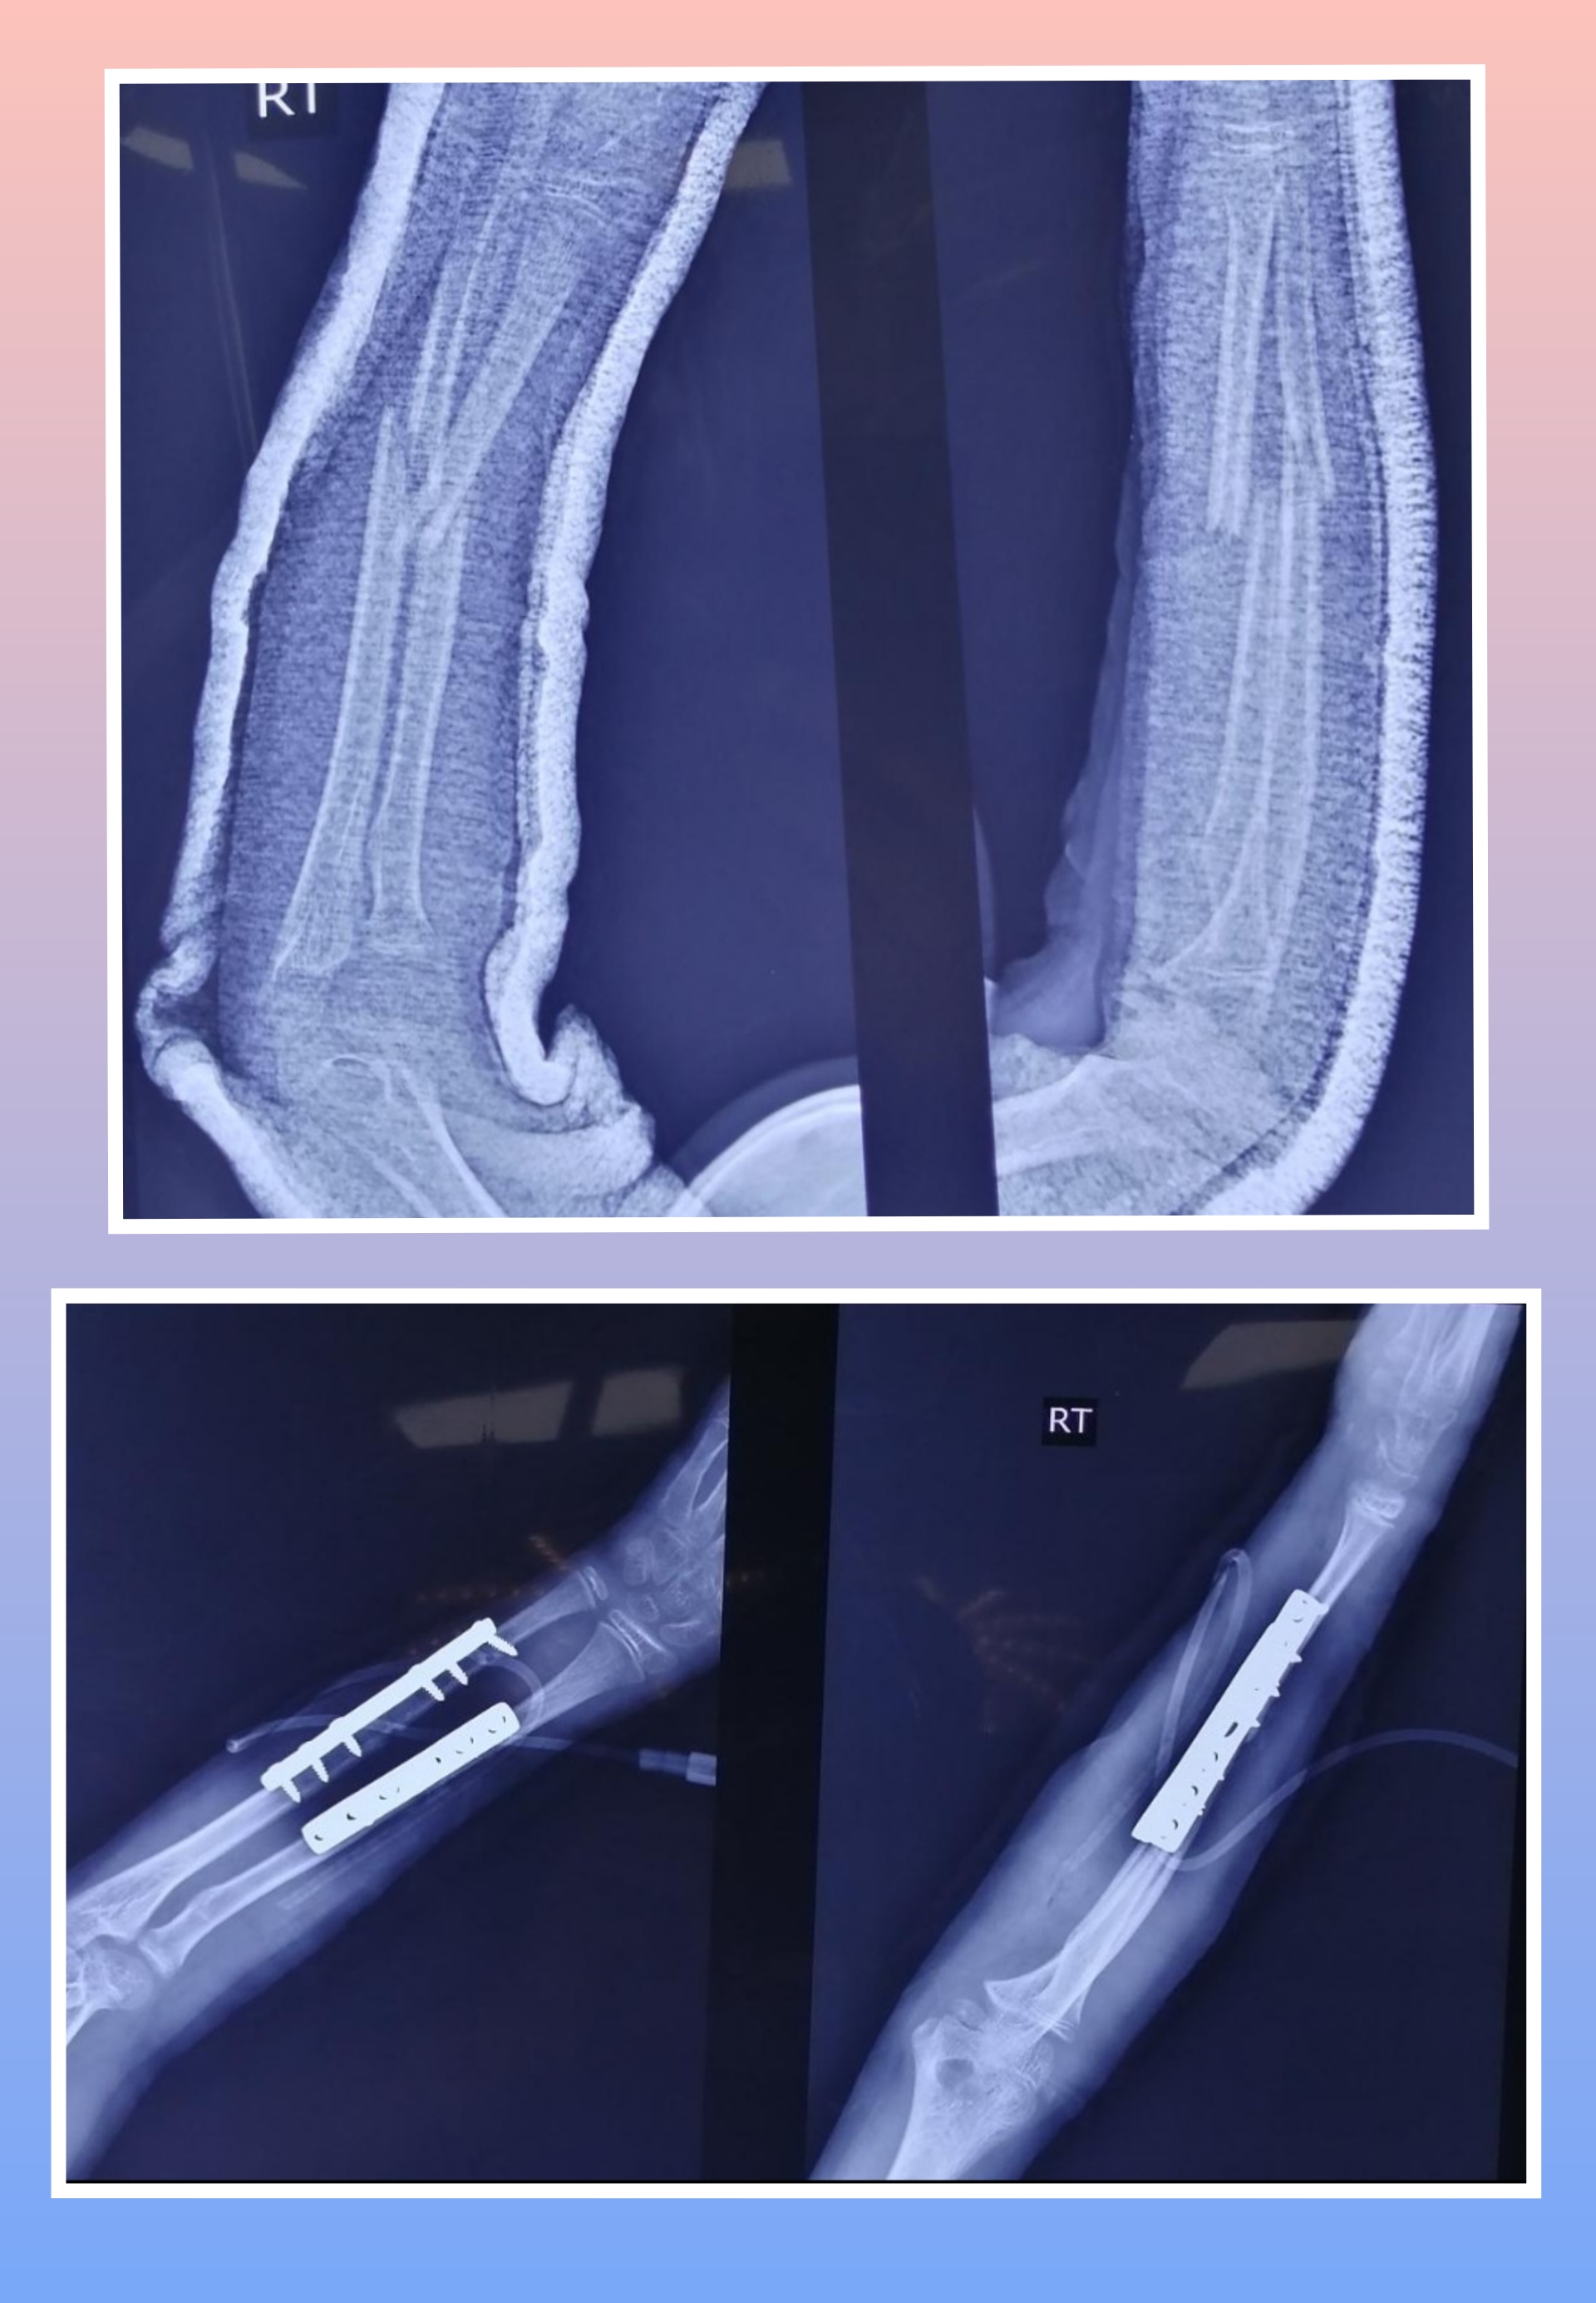

X-ray